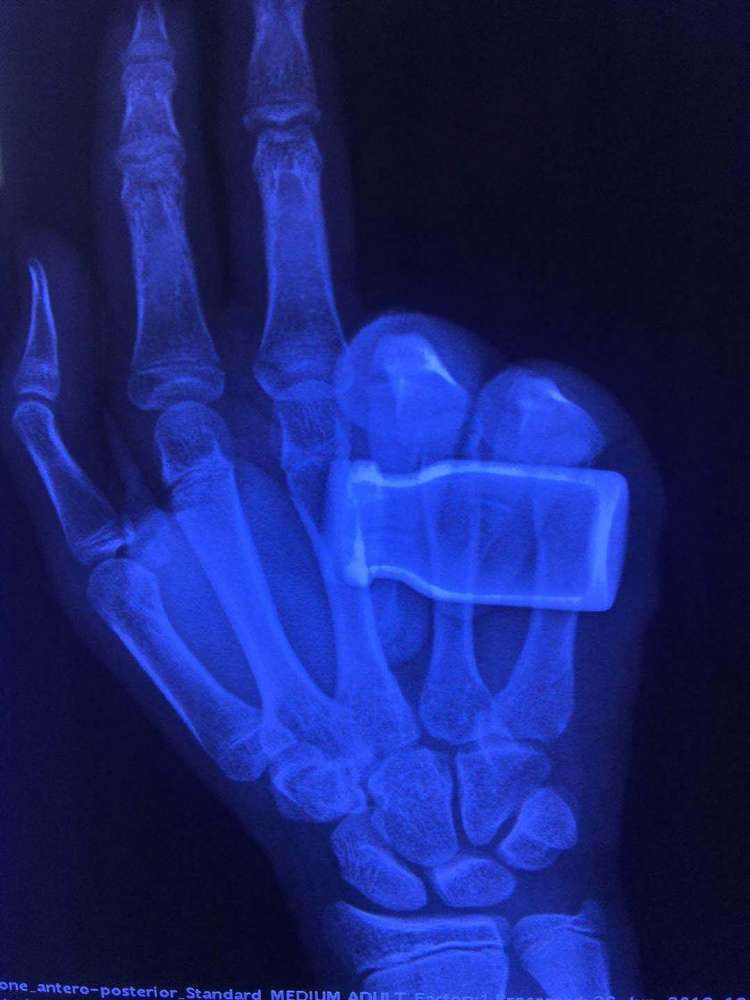

"拳击手"骨折了解一下,不用开刀,有时候一个小的安剖瓶就管用

【创伤篇】 023 "拳击者骨折"的治疗(病例展示)

拳击手骨折(第四掌骨骨折),请医生看看需要做手术吗?